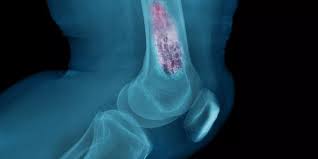

في مقالنا بعنوان "ما هي إصابة ليسفرانك؟ ما هي أعراضها؟ كيف تُعالج؟"، سنتناول تفاصيل هذه الحالة....